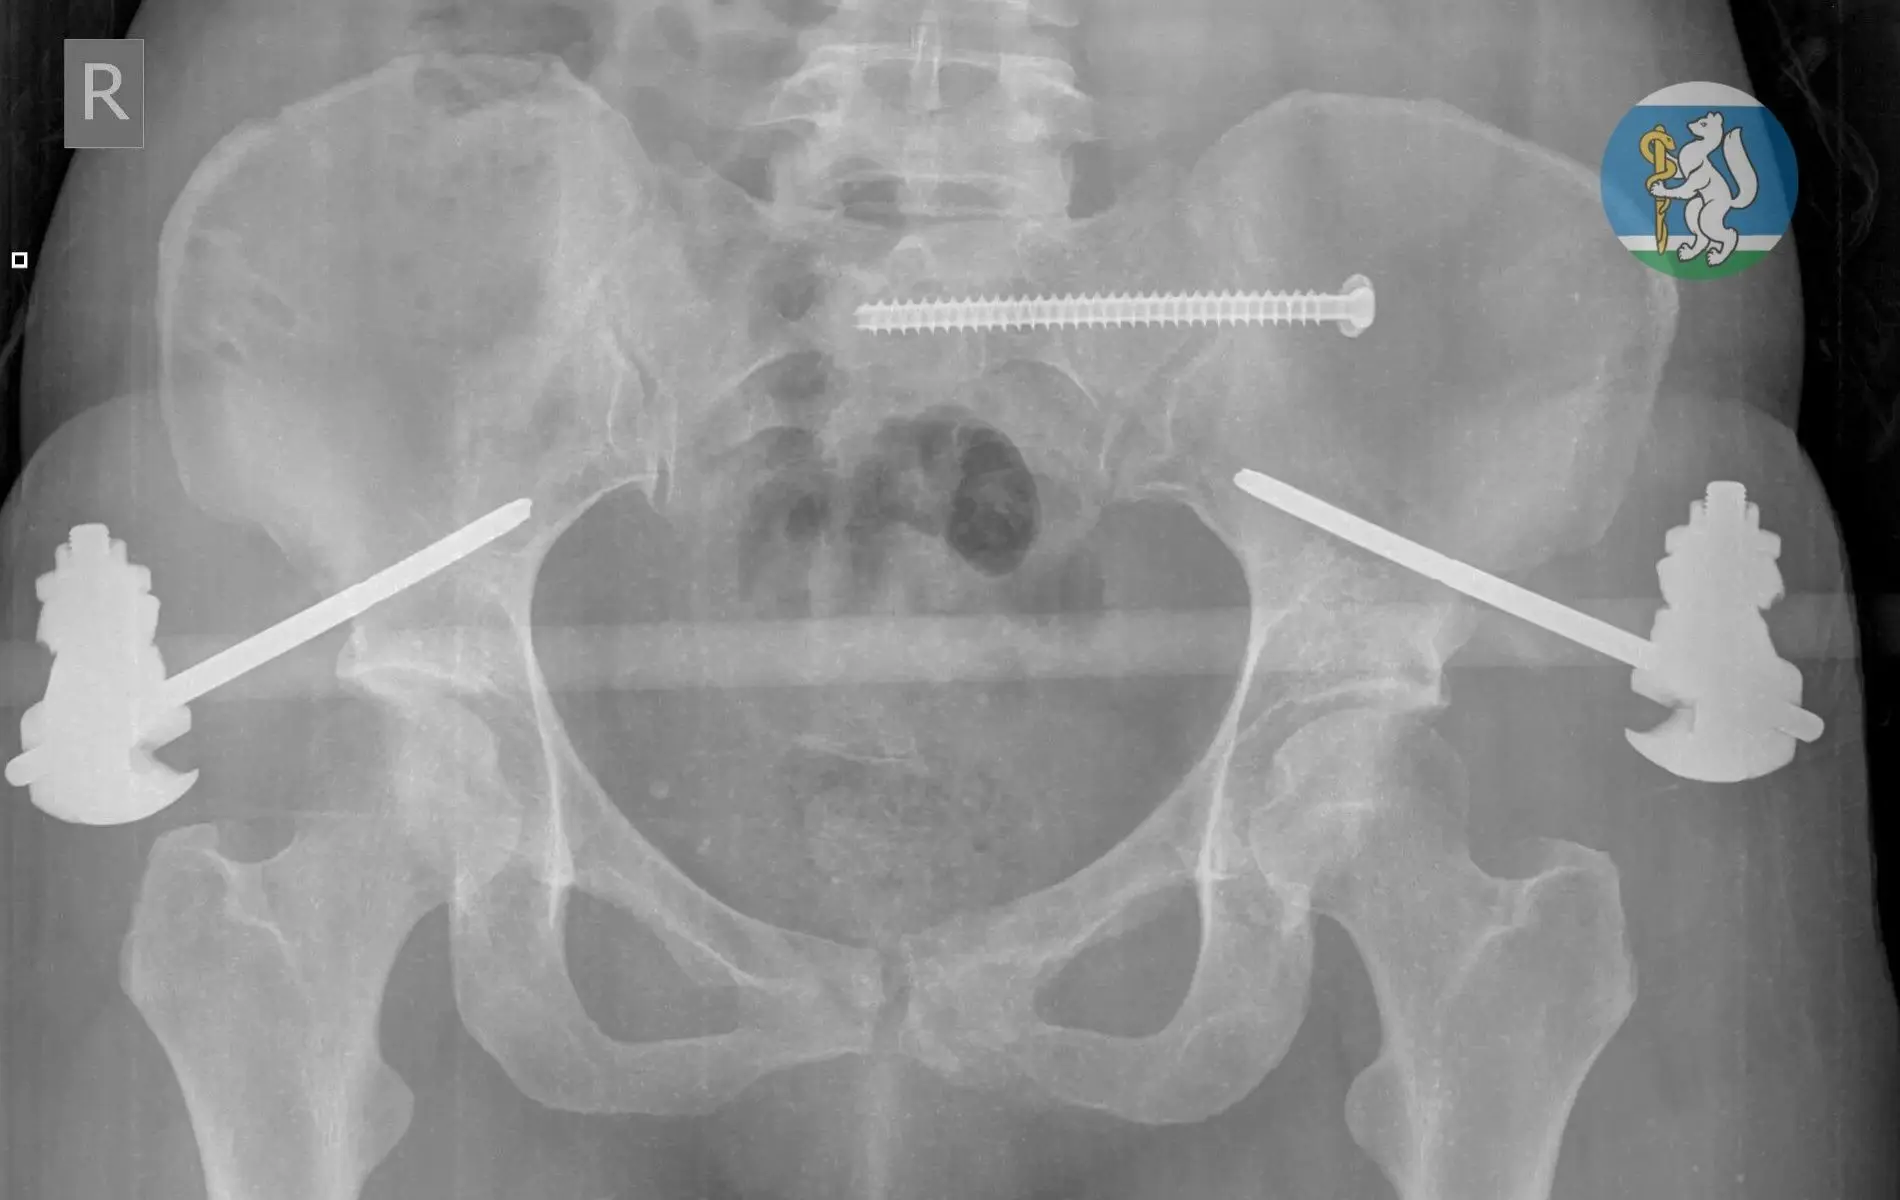

🦴 Точность до миллиметра: как уральские онкологи возвращают полноценную жизнь после сложных диагнозов

Онкоортопедия — одно из самых сложных направлений в медицине. Здесь нельзя допустить ошибку: на кону не просто удаление опухоли, а возможность человека снова ходить, работать, жить полноценно. В Свердловском онкологическом диспансере развивается передовая технология, которая меняет правила игры: замена поражённых костных сегментов высокоточными индивидуальными имплантами.

🤖В настоящее время для пациентов моделируют индивидуальные импланты, которые затем изготавливают на производстве. С 2024 года профильные специалисты учреждения здравоохранения выполнили пять вмешательств с полным замещением имплантом удалённой костной ткани.

Одним из недавних подобных случаев стало выявление новообразования у свердловчанки спровоцировало патологический перелом бедренной кости при обычной домашней нагрузке. После углублённой диагностики было принято решение провести органосохраняющую операцию, в ходе которой 20 сантиметров поражённой кости заменили индивидуальным титановым эндопротезом, смоделированным медиками на основе послойной компьютерной томографии и отпечатанным на заводе.

(на нашем фото)

🔥После успешной операции, которая длилась 5,5 часов, пациентка находится в раннем реабилитационном периоде и, несмотря на сложность и обширный объём хирургического вмешательства, передвигается самостоятельно.